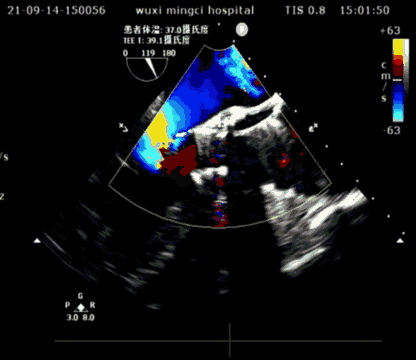

患者为81岁高龄男性,因反复胸闷气喘近3年,再加重10天入院,既往有高血压病史20余年,心脏彩超显示主动脉瓣瓣叶明显增厚伴钙化,最大峰值流速4.3m/s,最大跨瓣压差75mmHg,平均跨瓣压差40mmHg,主动脉瓣舒张期可见轻度反流,提示主动脉瓣重度狭窄伴轻度关闭不全。

超声短轴

超声长轴

瓣膜植入后,压差从术前70mmHg降至10mmHg以下,瓣膜形态良好,手术圆满成功。